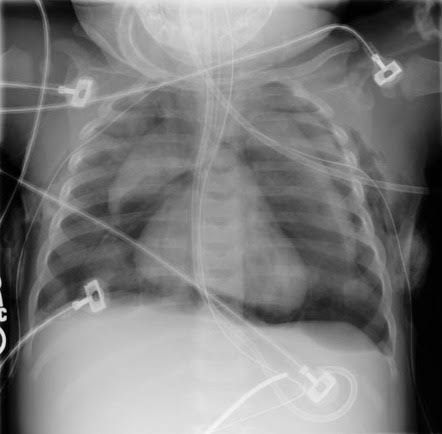

The spinnaker sign (also known as the angel wing sign) is a sign of pneumomediastinum seen on neonatal chest radiographs. It refers to the thymus being outlined by air with each lobe displaced laterally and appearing like spinnaker sails. This is distinct from the sail sign appearance of the normal thymus